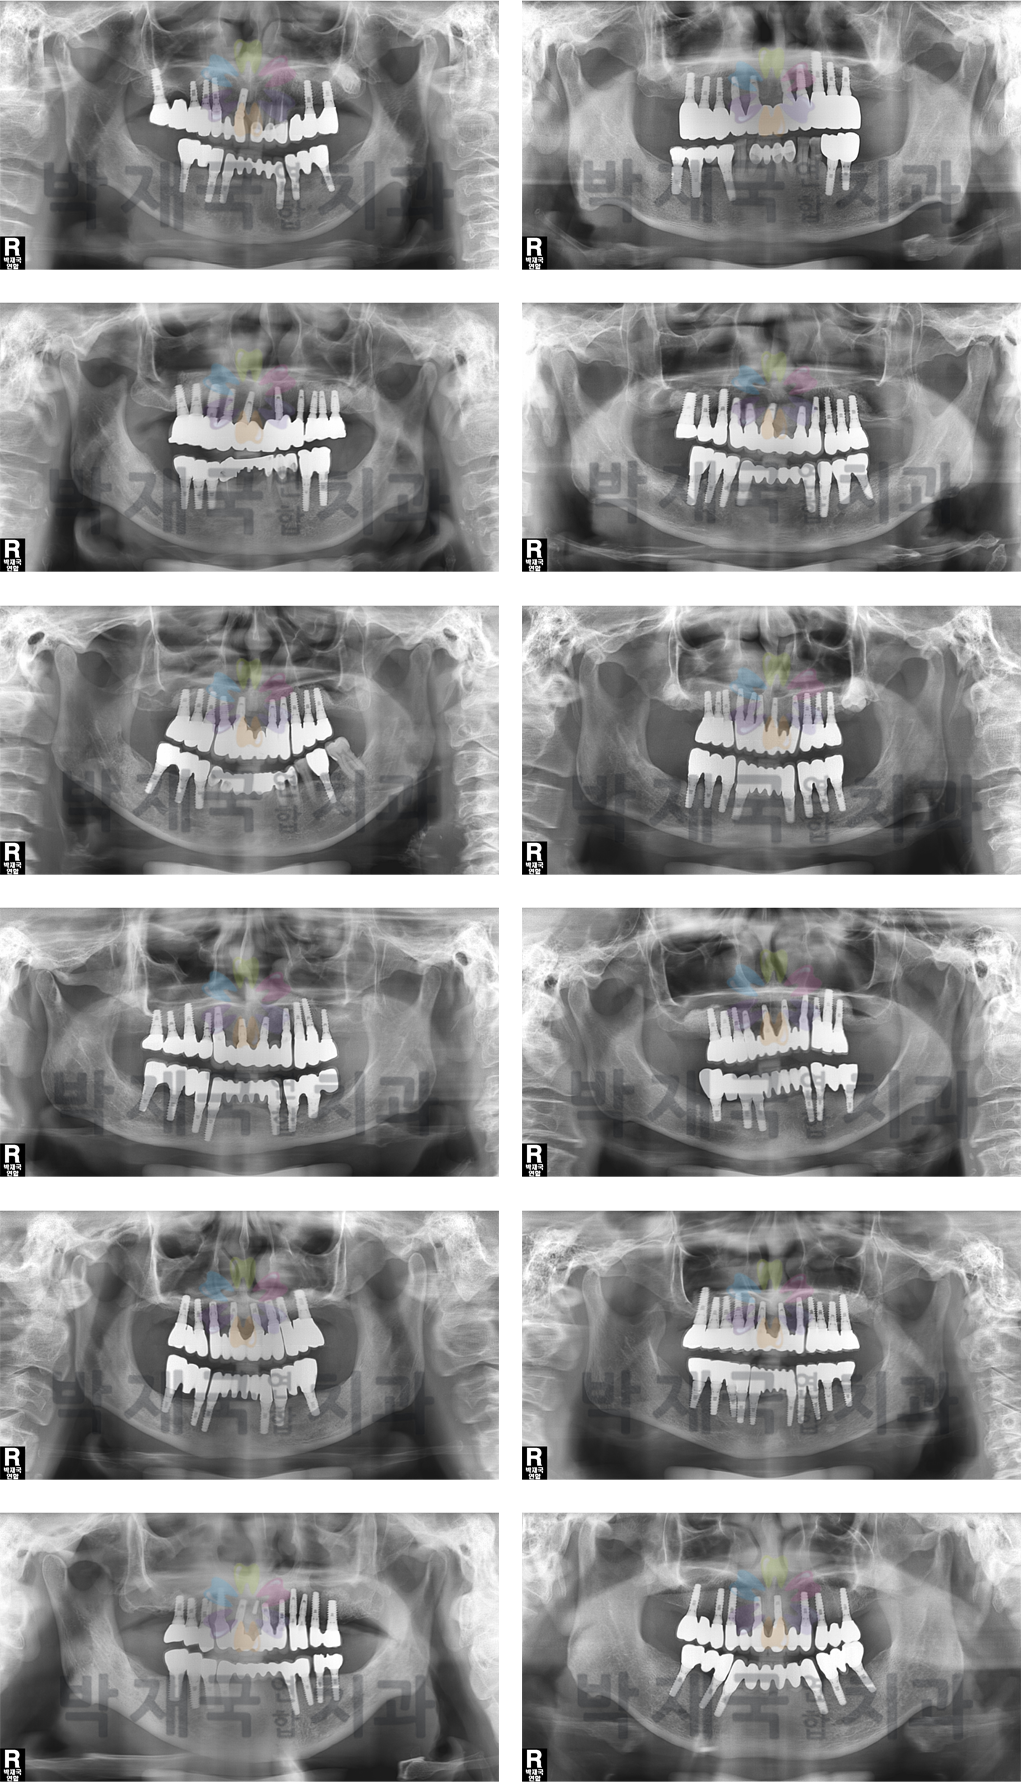

Àüü ÀÓÇöõÆ® »ç·Ê

implant clinic